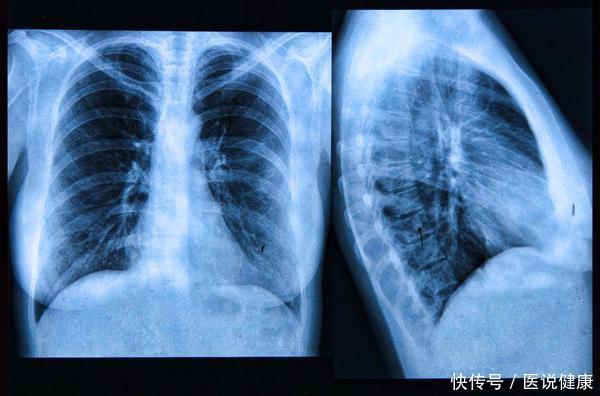

肺癌是一种对身体伤害非常大的恶性疾病,由于患病晚期会出现严重的呼吸障碍,因此人们往往对肺癌有一定的恐惧心理;

实际上只要能够在早期发现癌症的出现,并且及时进行针对性治疗,就能够有助于减少肺癌对身体的影响,增加治愈率,不过由于肺癌早期很容易被与其他疾病混淆;

想要能够辨别早期肺癌与其他疾病,除了能够通过症状来看,实际上肺癌的症状很难通过休息和常规的用药就得以缓解,而且会导致人的精神状态出现快速的衰退,同时还可能会出现食欲减退、消化能力下降的情况,可以选择定期的进行肺部的检查,有助于尽早的发现癌症发生的趋势,减少患病的可能性,有助于保持身体的健康。